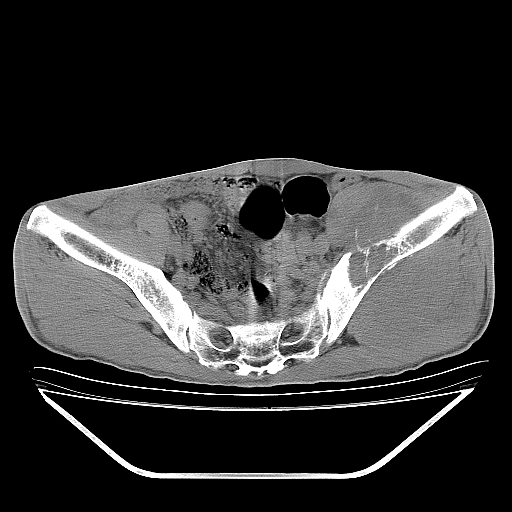

以下是引用天南地北在2007-10-4 18:01:00的发言:[br][br]考虑左髂部恶性肿瘤(溶骨性骨质破坏+软组织肿块影+残留骨质);以滑膜肉瘤可能性大。[br]建议穿刺活检

以下是引用liuyue在2007-10-4 23:38:00的发言:[br]左髂部恶性肿瘤,建议穿刺活检,或先做肺部检查,除外肺癌转移之可能。